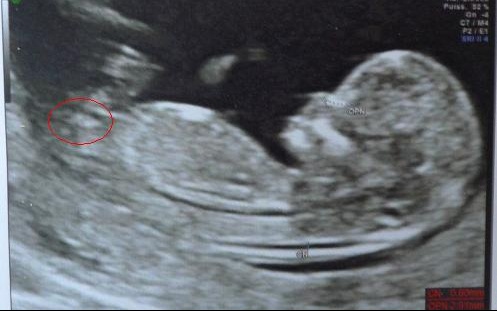

Savoir le sex du bebe echographie

Savoir le sex du bebe echographie-1 Test des mainsTout le monde ira de ses prédictions Pourtant, ce n'est que l' échographie qui vous révélera ce grand secret En attendant ce jour, voici 15 trucs pour prédire le sexe de bébé Attention!

Mais prudence, tout dépend du moment où l'échographie est réalisée et du temps que le praticien prend pour examiner le sexe Sachant que la première échographie a un objectif bien défini (nombre de fœtus et localisation, vitalité du fœtus, clarté nucale , anatomie), l'identification du sexe n'est clairement pas la prioritéCette façon de faire estelle fiable ?Fille ou garçon comment savoir ?

J'ai récemment écrit un article sur les différentes stratégies pour connaître le sexe du bébé dans le ventre de sa maman et si tu as été assidue, tu auras retenu que tu ne pourras être fixée qu'à partir de la deuxième échographie obligatoire, celle que tu fais au cours du 5ème mois de grossesse Cela dit, « 5 mois, c'est loooong !Comment savoir si on est enceinte d'une fille ou d'un garçon?Que des histoires de grandsmères et des mythes étranges, mais de quoi passer le temps avant le grand jour!